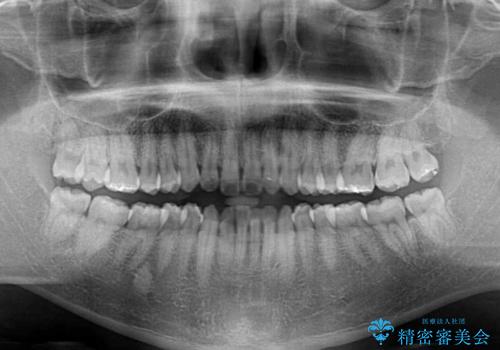

前歯のデコボコはインビザラインで十分に対応可能と判断できましたが、咬合力が強いため、臼歯(特に右側)の交叉咬合はインビザライン単体では困難と思われました。

まずはインビザライン単体で矯正治療を開始し、交叉咬合が改善されない場合にはアンカースクリューなどの使用を検討することとしました。

インビザライン単体では右側の交叉咬合を解消することができなかったため、アンカースクリューを併用して咬合を改善させました。